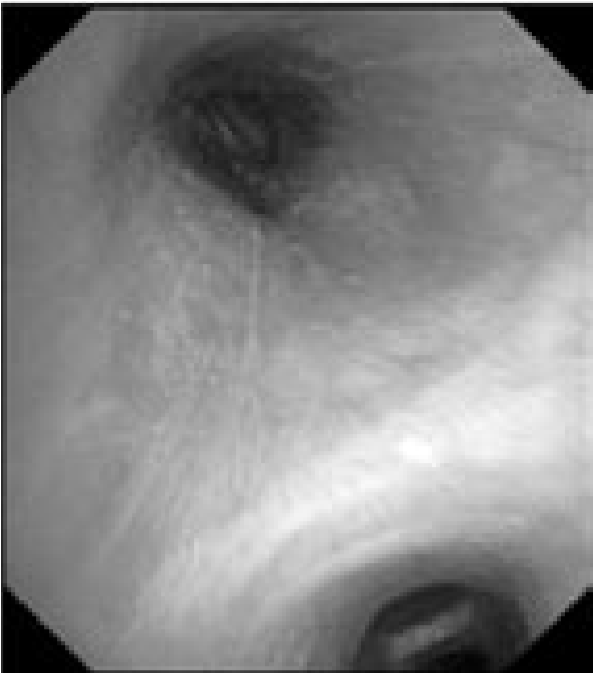

На втором этапе пациенту выполнена эндосонография средостения чреспищеводным доступом эхобронхоскопом Olympus BF UC180 (Olympus Corp., Japan) с применением ультразвукового центра EU-ME 1 (Olympus Corp., Japan). В ходе исследования в бифуркационной области визуализируется солитарный внутригрудной лимфатический узел (ВГЛУ) овоидной формы, размером 20×22 мм, с четкими контурами, слабой васкуляризации сосудами мелкого калибра, гетерогенной плотности, с зонами некроза, эластичный при пальпации инструментом (рис. 3).2

Рис. 3. Эндосонография средостения пациента А.: а – ультразвуковая картина лимфатического узла в бифуркационной области, в средней части лимфоузла определяется зона гипоэхогенеза (некротические массы); б – тот же узел, цветовое допплеровское картирование позволило определить зону васкуляризации в капсуле узла и выбрать оптимальную траекторию для выполнения тонкоигольной пункции; в – ультразвуковая картина перед проведением тонкоигольной биопсии – четко визуализируется дистальная часть оплетки иглы, с характерной акустической тенью (на 2 часа), детально различим гипоэхогенный участок в ткани лимфоузла (некроз).

Пациенту под контролем эндосонографии выполнено две серии пункций лимфоузлов группы 7 иглой Cook Echotip ProCore 22G (Cook Medical, Ireland). Полученный диагностический материал был направлен на морфологическое, цитологическое исследования, микробиологическое исследование (культуральное и молекулярно-генетическое) для верификации диагноза. Заключение по результатам эндосонографии: аденопатия средостения, более характерная для некротического поражения лимфоузла (туберкулезный лимфаденит?). Общая длительность комбинированного двухэтапного эндоскопического исследования составила 21 мин. Во время исследования и после него осложнений не отмечено2